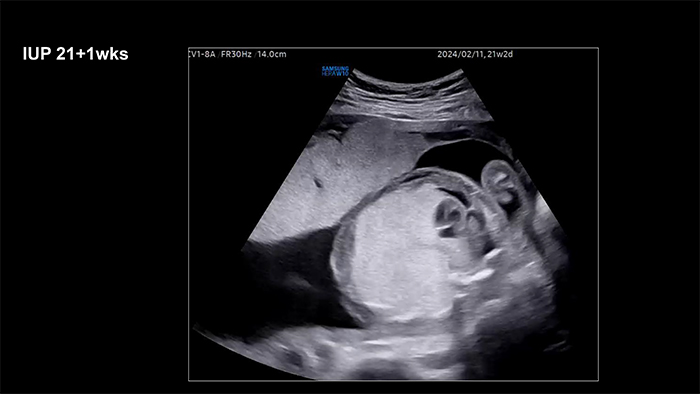

A 35-year-old multigravida was referred at 21.2 weeks of gestation due to a suspected large mass in the left thoracic cavity, accompanied by fetal ascites.

Ultrasonography revealed a 53 x 38 mm hyperechoic lesion in the left thoracic cavity with an inverted diaphragm. The mass was supplied by the pulmonary circulation.

The heart was severely compressed to the right. Skin edema and extensive ascites were observed, indicative of fetal hydrops.

Based on these findings, congenital pulmonary airway malformation (CPAM) or unilateral bronchial atresia was suspected. At 25 weeks of gestation, magnetic resonance imaging confirmed a diagnosis of left unilateral bronchial atresia.